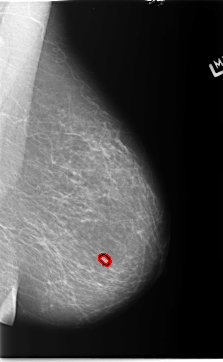

B_3154_1.LEFT_MLO

B_3154_1.LEFT_CC

LEFT_MLO LINES 5792 PIXELS_PER_LINE 3560 BITS_PER_PIXEL 12 RESOLUTION 50 OVERLAY

FILE: B_3154_1.LEFT_MLO.OVERLAY

TOTAL_ABNORMALITIES 1

ABNORMALITY 1

LESION_TYPE MASS SHAPE OVAL MARGINS CIRCUMSCRIBED

ASSESSMENT 3

SUBTLETY 4

PATHOLOGY BENIGN

TOTAL_OUTLINES 1

BOUNDARY

FILE: B_3154_1.LEFT_CC.OVERLAY